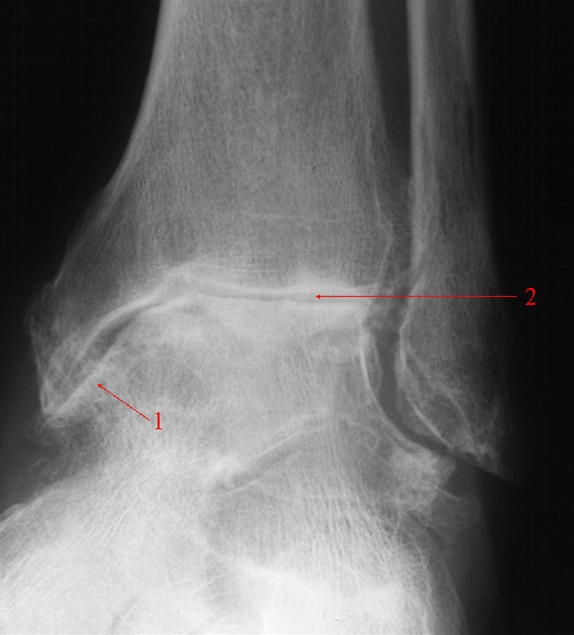

Ankelartrose, skråoptagelse

Svær slidgigt (artrose) i et ankelled med fortætning af knoglen - kaldet sclerosering (1) og reduceret bruskhøjde i leddet (2).